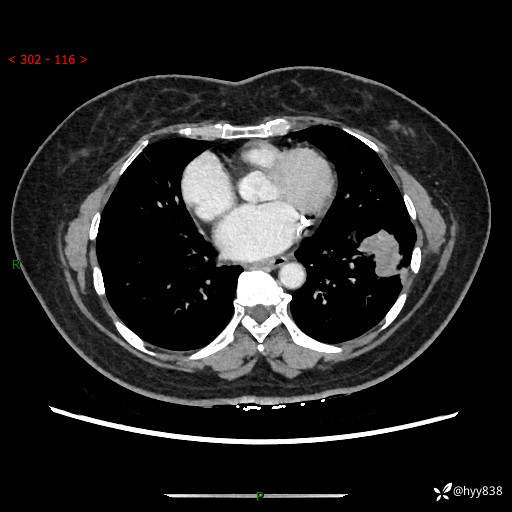

【现病史及既往史】:患者自诉2月前体检发现肺结节(左肺下叶约17mm,右肺上叶4mm),未予特殊处理,2024-10-12当地市第五医院门诊复查胸部CT提示右下肺结节(大小约3.3cm*3.9cm),患者无咳嗽、咳痰,无畏寒、发热、盗汗,无咯血,无胸闷、胸痛、呼吸困难,无恶心、呕吐,无腹痛、腹胀、腹泻等不适,现为求进一步诊治,门诊以“孤立性肺结节”收住我科。 患者本次起病来精神、食欲、睡眠尚可,大小便正常,体力、体重无明显变化。

【检查】:胸部CT增强检查